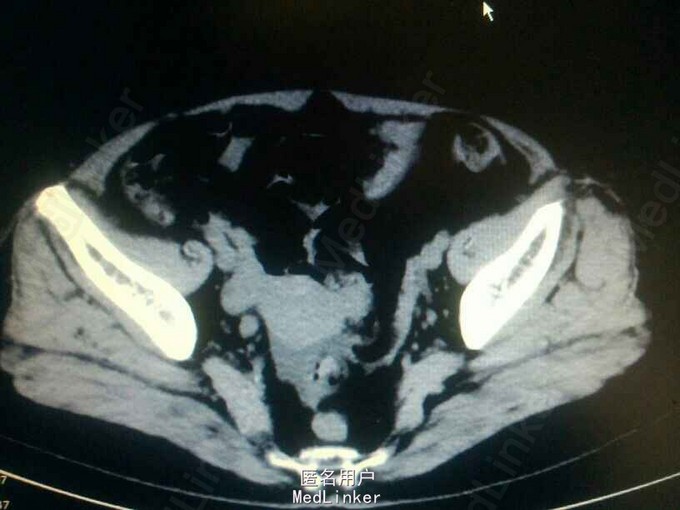

查体:无明显阳性体征! 辅助检查:CTU提示:右侧输尿管下段占位?输尿管镜检,右侧输尿管下段新生物,约1*1cm,病检示高级别浸润性尿路上皮癌?

右侧输尿管下段癌